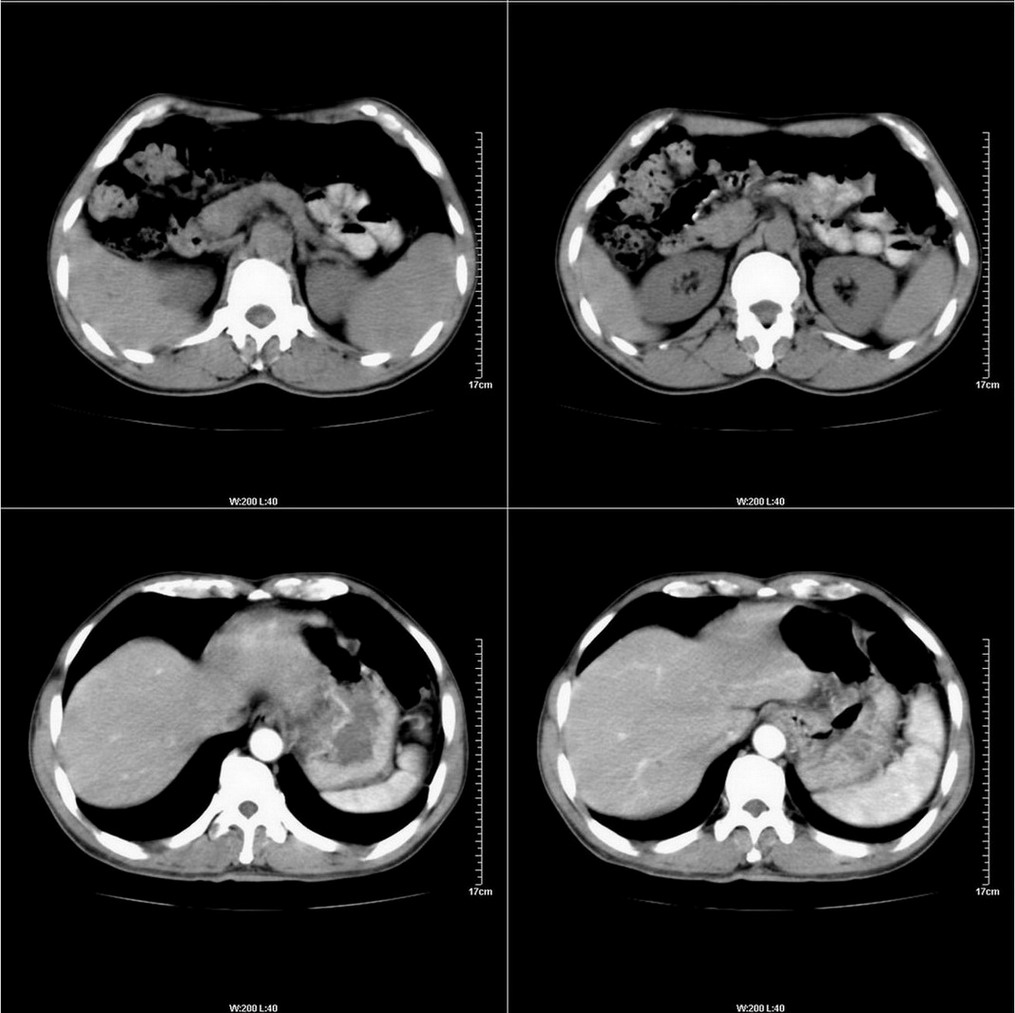

标题: CT14220:男性,59岁。腹部疼痛不适半年余。 [打印本页]

标题: CT14220:男性,59岁。腹部疼痛不适半年余。

胃壁弥漫增后,考虑胃炎溃疡

建议结合胃镜或钡餐检查,考虑胃底贲门癌可能性大。

考虑:1、肝右叶下部小囊肿;

2、胃可能为准备充盈不良所致,必要时请胃镜进一步检查。